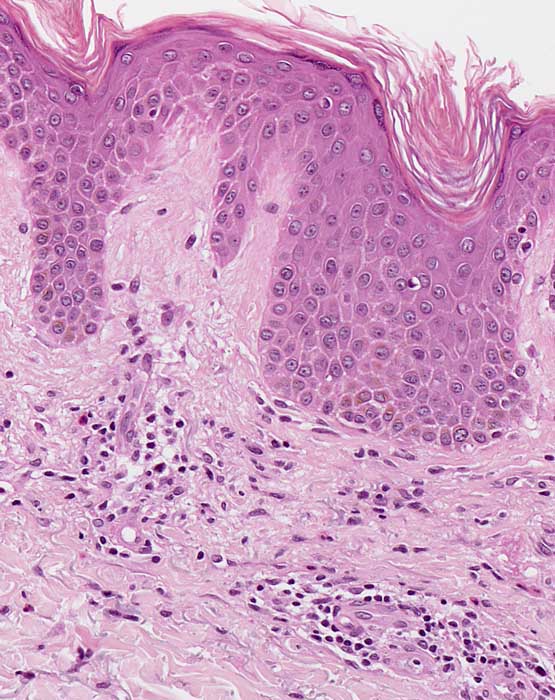

Entzündliche Hautreaktion mit Spongiose. Die Spongiose ist definiert als interzelluläres Ödem von Epidermis und/oder Adnexepithel, erkennbar an der Verbreiterung der Interzellularräume im Epithel. Bei gering ausgeprägter Spongiose stehen benachbarte Keratinozyten über verlängerte Interzellularbrücken noch miteinander in Kontakt, während bei stärkerer Ausprägung die desmosomalen Verbindungen dem Ödem nicht mehr standhalten und rupturieren, so dass sich die Zellen voneinander lösen und ein intraepitheliales Bläschen (spongiotisches Bläschen) entsteht. Dieser Prozess ist Ausdruck einer Entzündungsreaktion, die in der Regel durch Lymphozyten, seltener durch eosinophile oder neutrophile Granulozyten vermittelt wird. Die beteiligten Zellen sind im betroffenen Epithel (lymphozytäre Exozytose) und in der oberen Dermis nachweisbar. Verteilungsmuster und Zusammensetzung der Entzündungszellen können einen Hinweis geben auf die Ursache des spongiotischen Reaktionsmusters. Man unterscheidet klinisch und histopathologisch unterschiedliche Stadien (akut-subakut-chronisch).

Histologisch zeigen akute Ekzeme eine ausgeprägte Spongiose mit intraepithelialer Bläschenbildung, eine Parakeratose und Krustenauflagerungen, im chronischen Stadium eine Verminderung der Spongiose, eine Akanthose und Hyperparakeratose. Bei alten Läsionen können Parakeratosehügel und eine Epidermishyperplasie der einzige Hinweis auf eine spongiotische Dermatitis sein. Die Epidermishyperplasie ist teilweise eine Folge des chronischen Reibens und Kratzens der juckenden Haut. Das Entzündungsinfiltrat in der oberen Dermis besteht aus Lymphozyten und Histiozyten, zum Teil auch aus neutrophilen und eosinophilen Granulozyten. In der Epidermis dominieren Lymphozyten (lymphozytäre Exozytose). Akute, subakute und chronische Veränderungen können beim gleichen Patienten nebeneinander vorkommen.

Morphologische Merkmale:

• Verdickte Epidermis (Akanthose)

• Spongiose (interzelluläres Ödem der Epidermis)

• Spongiotische Vesikel (intraepitheliale Bläschenbildung)

• Parakeratotische Verhornung (Verhornte Zellen mit erkennbaren Zellkernen)

• Ödem der papillären Dermis (Aufhellung)

• Oberflächlich dermales perivaskulär betontes Entzündungsinfiltrat

• Lymphozyten, Histiozyten, neutrophile und eosinophile Granulozyten